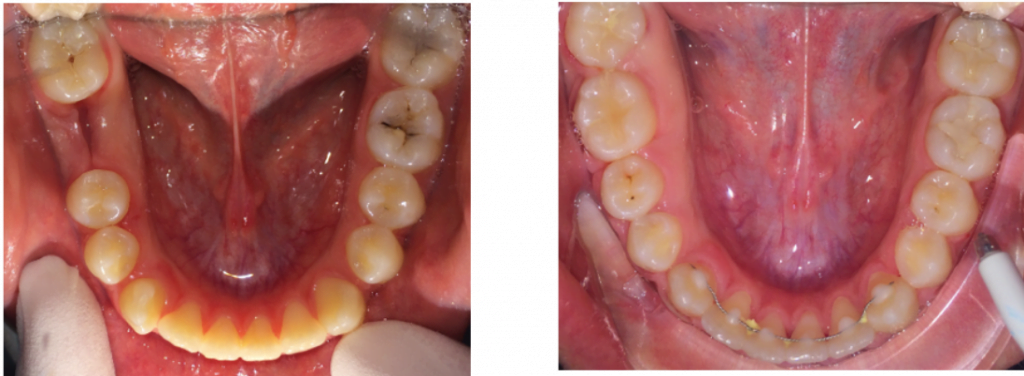

Ha csak esztétikai kezelés történik, ehhez elég a hat frontfog mozgatása, így ebben az esetben ezeket a fogakat foglalja magában a részleges készülék. Előfordulhat, hogy csak egy vagy pár fogra kiterjedő harapási eltéréssel állunk szemben, amikor elégséges ezen fogak mozgatása. Fogpótlásokhoz / implantátumokhoz történő előkészítéshez – fog felállítás, résnyitás, rés-zárás, stb. – is elégséges lehet egy részleges fogszabályzó készülék.

Természetesen az azonos fogíven levő többi fognak, illetve a másik fogív nem mozgatott fogainak rögzítése a részleges fogszabályzó alkalmazása mellett szükséges, akár fix összerögzítéssel, általában valamilyen, a nem mozgatott fogakra ragasztott és azokat stabilan tartó fémszállal, vagy kivehető segédkészülékkel, ún. mélyhúzott sínnel.